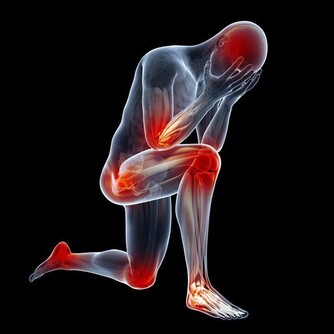

當我們的腎臟出現問題時,我們的身體會出現一些症狀,

這時,如果大家忽視這些症狀,就有可能早晨腎臟更為嚴重的病變。

下面小編給大家總結了一些關於腎臟出現問題時,我們身體出現的反應,希望大家及時發現問題,及時治療。

4、骨骼強壯:中醫認為,腎主骨,骨靠腎精滋養,腎好骨才好。腎氣衰敗會出現骨質疏鬆、腰酸背痛,甚至牙齒出現鬆動。

7、早起身體沒有浮腫:腎臟是人體代謝水分的器官,腎不好,水分就會蓄積。如果經常早起眼皮浮腫,或者雙腳、雙腿浮腫,都要考慮腎臟問題。

8、精神十足:當腎功能出現問題時,身體裡的廢物殘渣難以從尿液裡排泄出去,會出現精神不振、疲勞、沒勁兒的感覺。